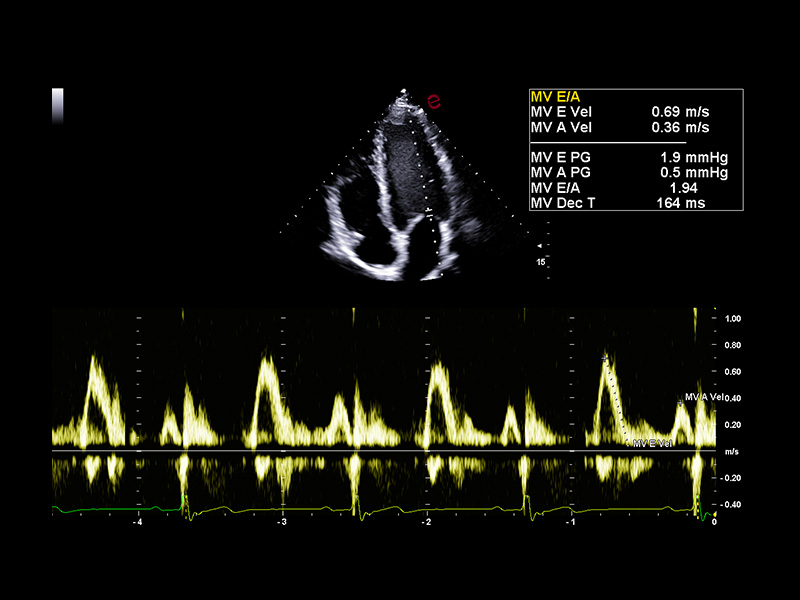

Esaote’s AutoEF and AutoCM tools are designed to bring a step ahead in the device use experience. With advanced AI algorithms, AutoEF automatically recognizes apical views and traces endocardial borders offering a proposal of left ventricular volumes and ejection fraction in just seconds. AutoCM complements this by automatically suggesting ventricular wall thickness, internal diameters, and derived values such as LV mass and fractional shortening directly from parasternal views. Moreover, AutoCM assists cardiologists by automatically recommending a calculation of the E/A wave ratio of the mitral valve, providing crucial information on diastolic function.

Together, these tools help clinicians to obtain accurate, guideline-aligned measurements in a fast way, enhancing diagnostic reliability. AutoEF and AutoCM automate key functional and structural measurements—such as ejection fraction, LV volumes, wall thickness, and LV mass— making a smooth workflow, especially in high-throughput clinics.